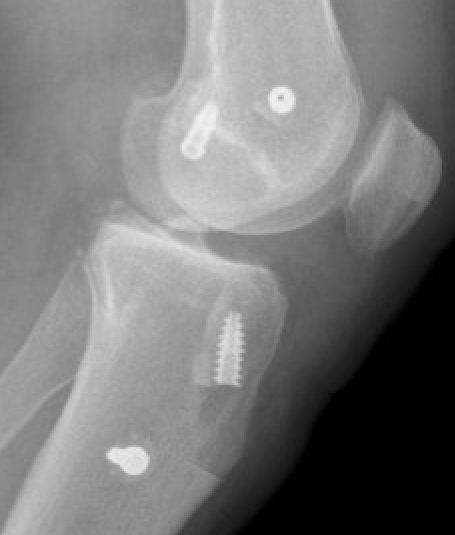

Bony MCL Avulsion

Elevate VMO and repair with staples or screw

Advancement of proximal MCL / POL with screw, and imbrication / tightening of POL

Tightening of proximal MCL / POL with sutures

Advancement of femoral MCL and staple / suture anchor fixation

3. Reconstruction of MCL and posteromedial corner

A. Single bundle anatomic allograft MCL reconstruction (no POL)